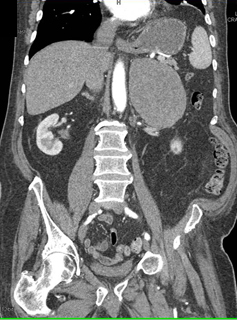

The least likely diagnosis in this case is

adrenal carcinoma

adrenal lymphoma

adrenal metastases

adrenal hematoma